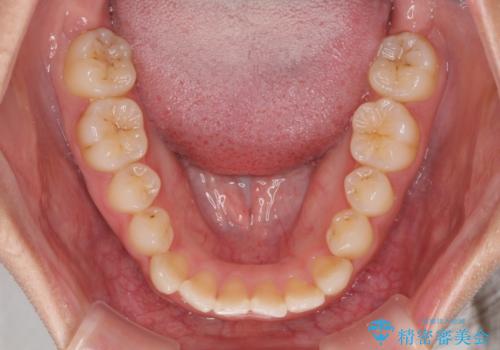

前歯のクロスバイトと変色した歯 ワイヤー矯正とセラミック治療

- 前歯のクロスバイトと神経を取り除いた後に変色してしまった前歯を気にして来院された患者様です。

ワイヤー矯正により矯正治療を行った後に、前歯の補綴治療を行うこととしました。